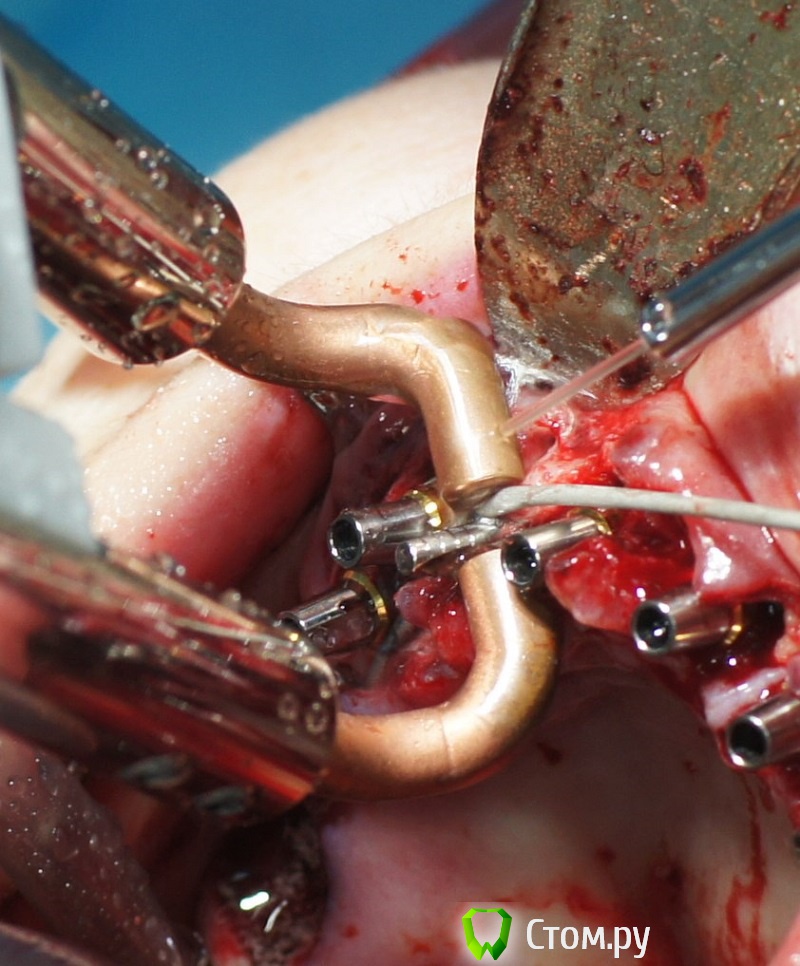

rin3225 Опубликовано 8 октября, 2014 Поделиться Опубликовано 8 октября, 2014 У пациента было желание сделать красивые зубы и улыбку!Проблема заключалась в массивной верхней челюсти , глубоком перекрытии и пациент не мог уйти без зубов! Отлив модели и выставив в центральную окклюзию было понятно, что без удаления всех зубов и поднятия прикуса с данной проблемой вопрос не решится. Обговорив все нюансы с пациентом,и получив согласие, было запланировано. заранее изготовлены акриловые протезы, предложено удаление всех зубов с одномоментной установкой имплантатов, внутриротавая сварка для первичной стабильности имплантатов и немедленная нагрузка 16 Ссылка на комментарий

КДБ Опубликовано 8 октября, 2014 Поделиться Опубликовано 8 октября, 2014 если не сложно-показания к внутриротовой сварке?какая была первичная стабилизация имплантатов?эти поперечные балки в поддесневой зоне,не будет ли здесь проблем?Спасибо. Ссылка на комментарий

rin3225 Опубликовано 8 октября, 2014 Автор Поделиться Опубликовано 8 октября, 2014 если не сложно-показания к внутриротовой сварке?какая была первичная стабилизация имплантатов?эти поперечные балки в поддесневой зоне,не будет ли здесь проблем?Спасибо.Показания как я писал для первичной стабильности имплантатов, немедленной нагрузки,и распределение нагрузки. По поводу первичной фиксации в разных участках была разная, кость 3-4 го типа от 20 до 30 То, что балки под десной, какие проблемы должны быть? Ссылка на комментарий

rin3225 Опубликовано 8 октября, 2014 Автор Поделиться Опубликовано 8 октября, 2014 Зачем так много имплантатов?Почему проволока приварена в поддесневом пространстве?Каким образом крепятся протезы? Ведь фиксация должна быть винтовая, а каркасс должен располагаться внутри протеза. Проволку можно преварить как под десной так и над десной, это не каркас протеза, протезы сьемные для соблюдения гигиены.В дольнейшем кострукция будет поменена на несьемные 1 Ссылка на комментарий

Дмитрий Никитюк Опубликовано 8 октября, 2014 Поделиться Опубликовано 8 октября, 2014 Да понятно мне всё. Просто я категорически не согласен с подобным решением. Концепция применения сварки, которая мне импонирует, позволяет уменьшить количество имплантатов; надёжно их мобилизировать, обеспечив абсолютную неподвижность даже тех имплантатов, где торк был недостаточным; изготовить и зафиксировать протезную конструкцию в день имплантации; удешевить конструкцию; обеспечить пассивную посадку конструкции с винтовой фиксацией; облегчить последующее изготовление постоянной конструкции. В Вашем случае применение сварки считаю неоправданным. Вы так и не ответили на вопрос, зачем так много имплантатов? Второй вопрос, как Вы будете извлекать приваренную дугу перед постоянным протезированием. Ответьте на эти вопросы прежде всего себе, и Вы поймёте, что заблуждались... 3 Ссылка на комментарий